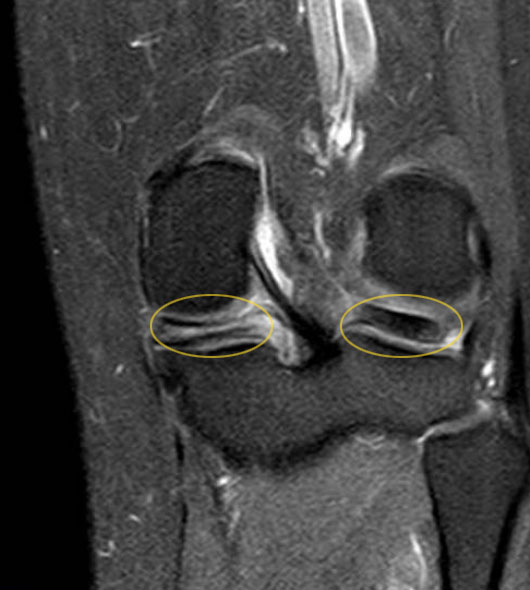

Magnetresonanztomographie bei Meniskusriss

Anders als das Röntgenbild, das vor allem Knochen darstellt, erstellt die MRT (Magnetresonanztomographie) detaillierte Bilder aller Weichteilgewebe. So kann der Kniespezialist den Zustand von Sehnen, Bändern und den knorpelähnlichen Menisken beurteilen. Besonders wertvoll bei der MRT-Untersuchung des Meniskusrisses ist die Möglichkeit, Verlauf, Länge und genaue Lage der Meniskusschäden im Detail in der Bildgebung darzustellen.